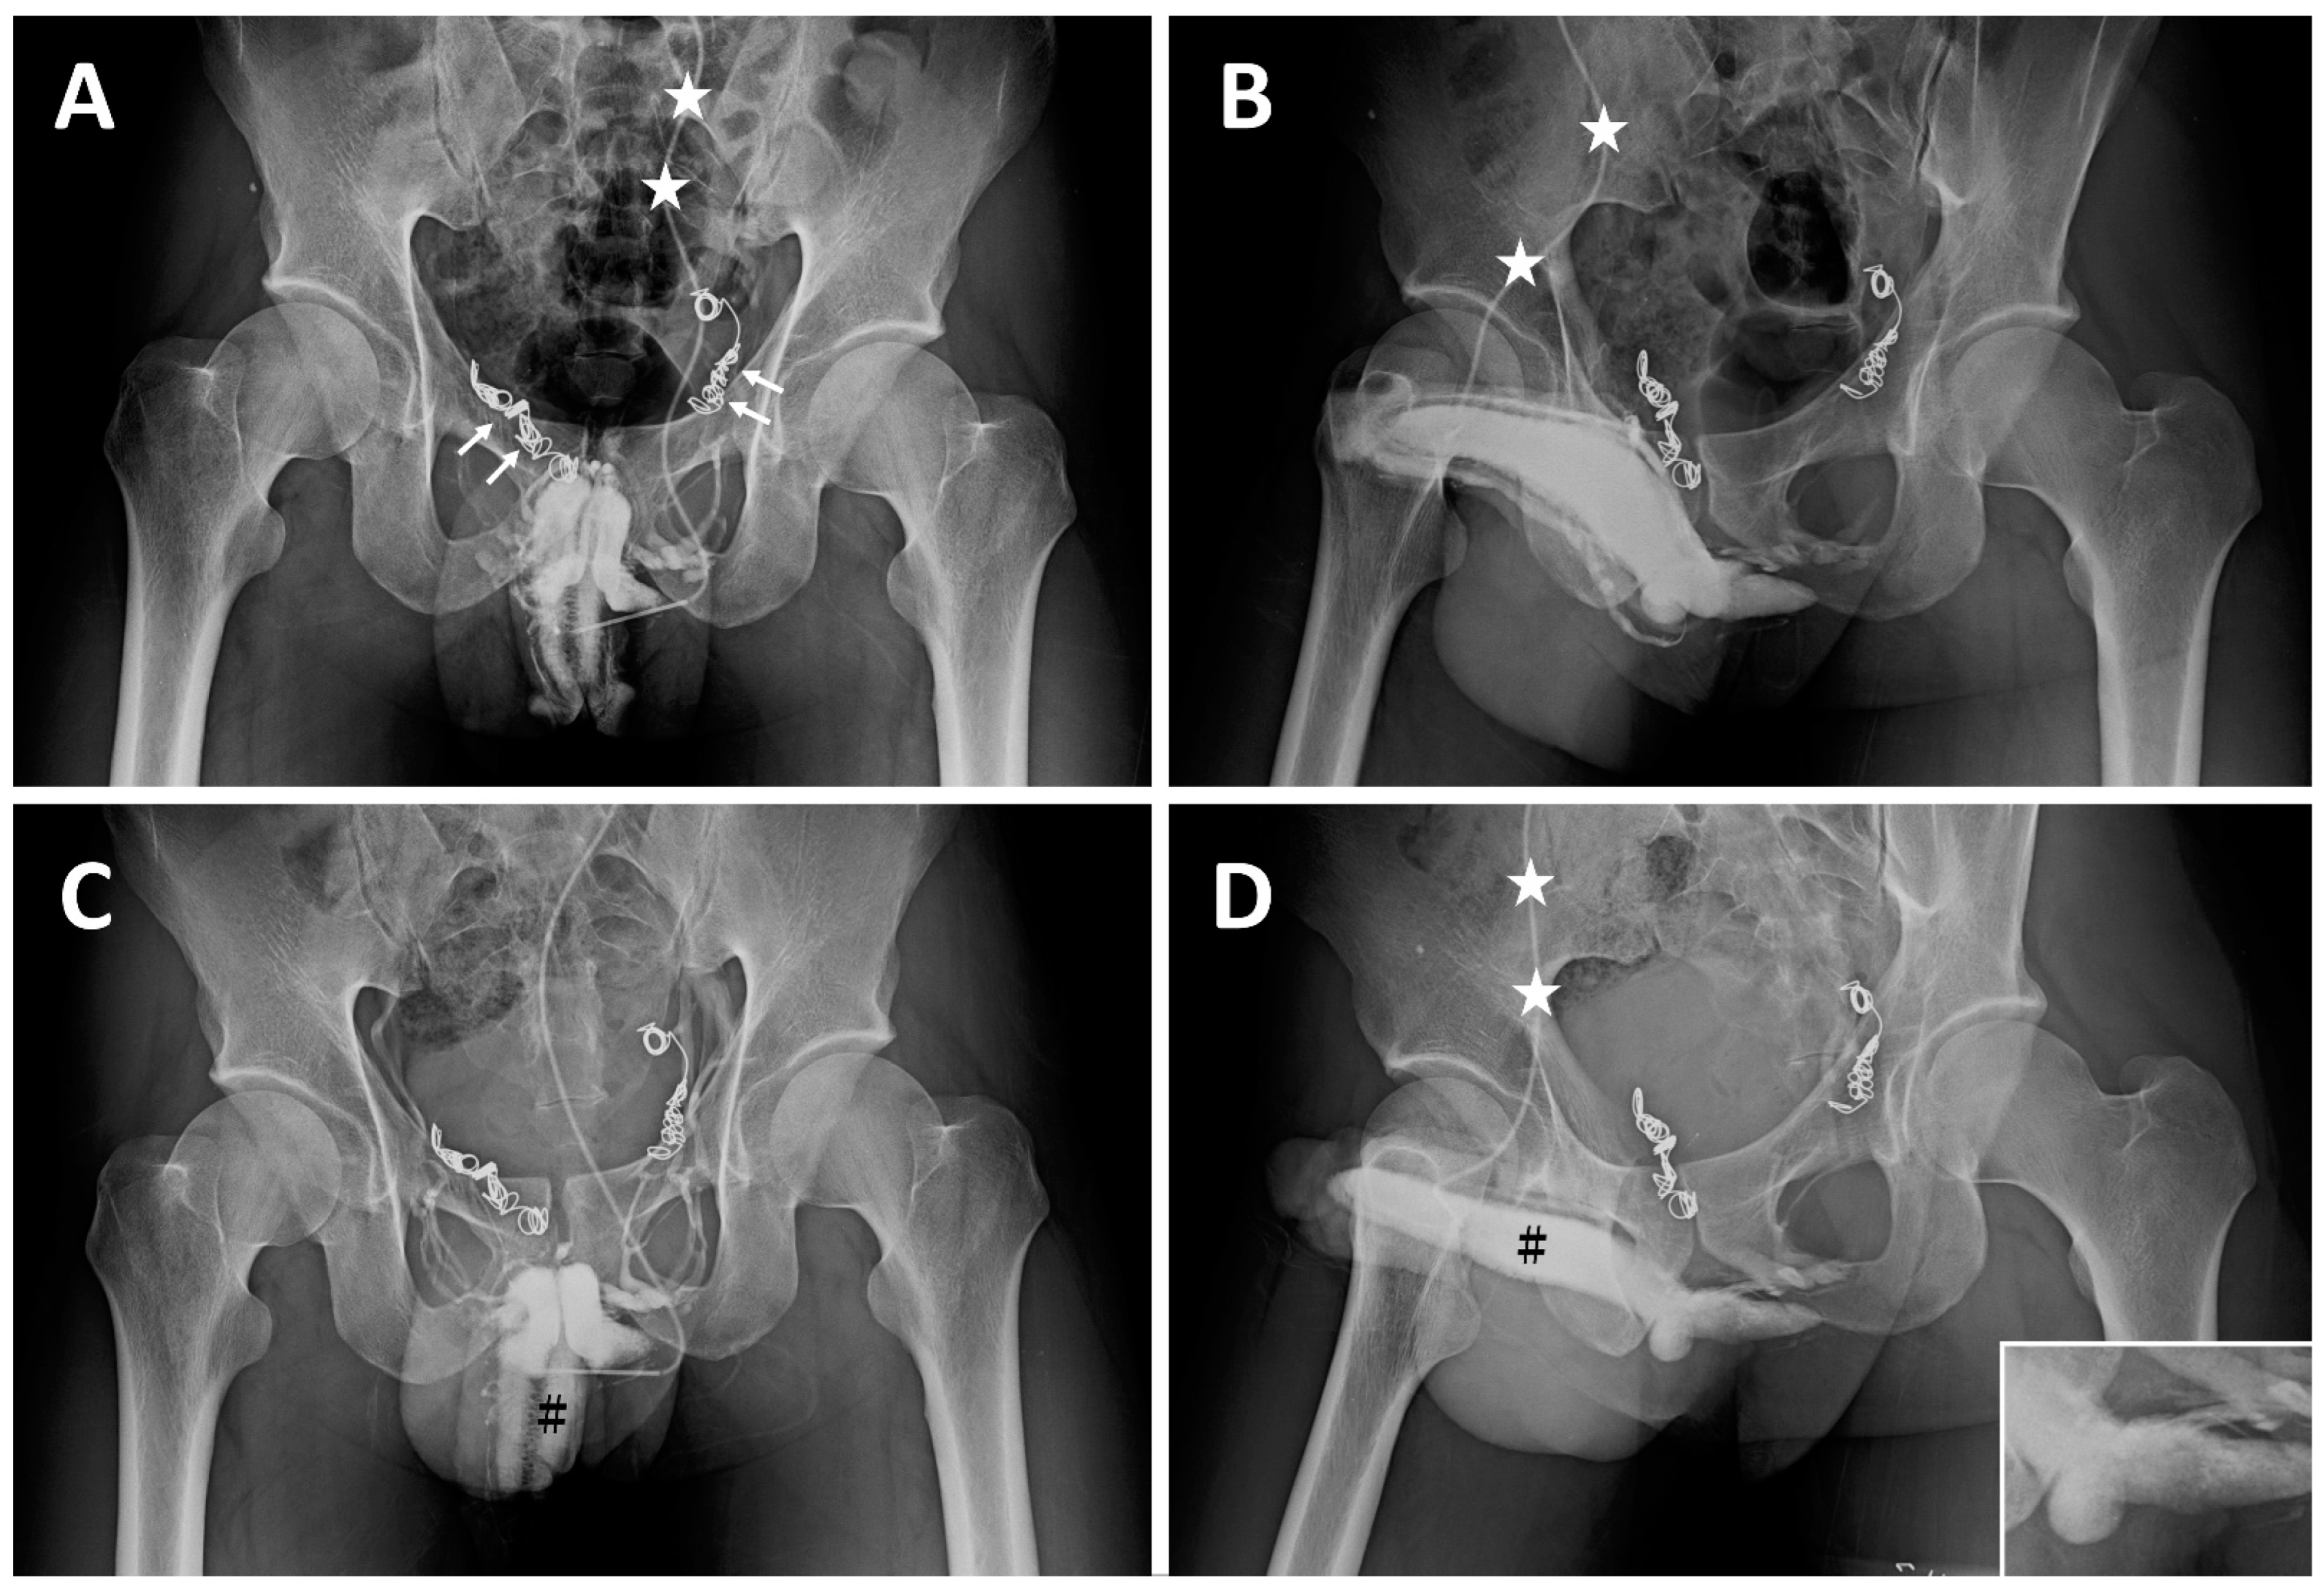

| ED a | 2008 | Early detumescence of rigid erection, position-dependent | A multiplanar diagnosis workup showed a veno-occlusive dysfunction. |

| CE(I) b | 2010 | Same | Acute chest pain was caused by the migration of a dumbbell-shaped coil to the right pulmonary artery. |

| CE(II) c | November 2012 | Same | A tapeworm-shaped coil was noted in the region of the right iliac vein at 90 degrees to the venous channel. |

| CE(III) d | May 2014 | Same | A pigtail-shaped coil was shown at the left internal pudendal vein level at 90 degrees to the venous channel. |